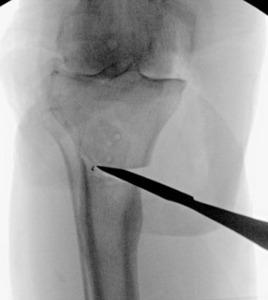

The two TTO cortical screws were removed. Attention then turned to the extra-articular deformity. Under biplanar fluoroscopic control an oblique medial open-wedge osteotomy was created six centimeters distal to the tibial plateau at the apex of the varus malunion (Figure 3). A laminar spreader was gently inserted and opened until a neutral mechanical hip–knee–ankle axis was achieved, as confirmed with an extramedullary alignment rod extending from the center of the femoral head to the center of the ankle mortise.

A surgical assistant steadied the correction by holding laminar spreader and distal leg during tibial preparation. The tibial canal was sequentially reamed to accommodate a 15-mm diameter, 150-mm press-fit stem. Standard measured-resection technique was used on the femur with an intramedullary guide set to 6˚ of valgus. Femoral rotation was set to 4˚ of external rotation relative to the posterior condylar axis and parallel to the trans epicondylar axis—an amount chosen to optimize patellar tracking without over-stuffing the lateral compartment. The tibial proximal cut was made perpendicular to the mechanical axis with a targeted posterior slope of 3˚. Initial tibial component rotation was referenced to the medial one-third of the tibial tubercle and patellar tendon trajectory.

Trial components were inserted and demonstrated balanced flexion and extension gaps and central patellar tracking without the need for lateral release. The tibia was subsequently punched after confirming appropriate rotation for adequate patellar tracking. Final implantation proceeded with pressurized cement for the posterior-stabilized femoral component and the tibial baseplate under tourniquet insufflation. The diaphyseal press-fit stem was again confirmed to span the osteotomy by more than two cortical diameters under fluoroscopic guidance (Figure 4). Autogenous cancellous graft harvested from the femoral chamfer cuts was tightly packed into the osteotomy gap and along the medial cortex. The patella was resurfaced with a medialized polyethylene button.